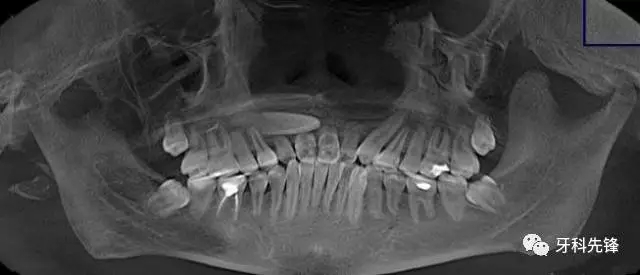

圖2.術前的CBCT檢查:11牙根幾乎完全吸收、12牙根吸收2/3. 21牙齒唇側牙根部分吸收。